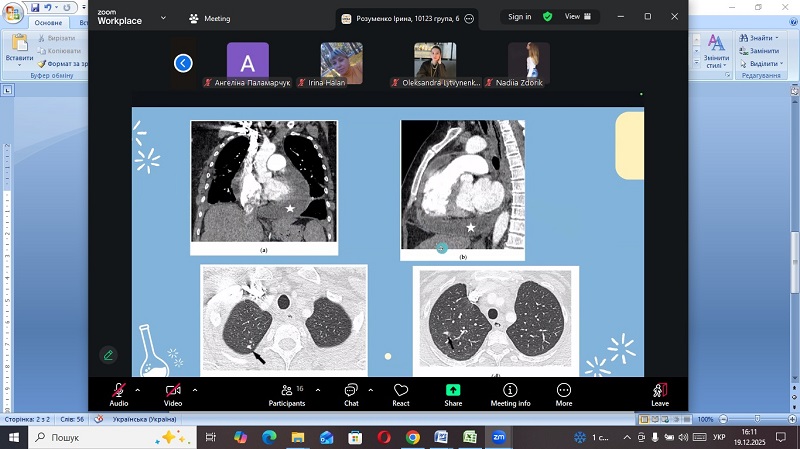

Про особливості перебігу туберкульозного перикардиту учасників проінформувала студентка 4 курсу Навчально-наукового інституту медицини НМУ імені О.О. Богомольця Ірина Розуменко. Доповідачка навела статистичні дані щодо країн з високим рівнем захворюваності та звернула увагу на частоту виявлення патології серед усіх випадків туберкульозу (1–2%). Спікерка зупинилася на диференційній діагностиці туберкульозного перикардиту з вірусним, бактеріальним та неінфекційним перикардитами, новоутворенням перикарду. Вона також розповіла про особливості клінічного перебігу хвороби, відмітила сучасні підходи до диференційної діагностики та зробила розбір алгоритмів лікування. У межах доповіді Ірина Розуменко окремо зупинилася на питаннях рентгенологічної (оглядовій рентгенографії, комп’ютерній томографії) діагностики. Значна увага була приділена дослідженням перикардіальної рідини із застосуванням біохімічних маркерів, молекулярно-генетичних тестів та перикардіальної біопсії.